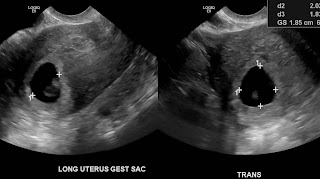

I picked up the CD from my ultrasound and also got a report.

The gestational sac is 1.7x2.02x1.83cm which corresponds to  gestational age of 6 weeks 2 days.

The fetal pole has a crown to rump length of 0.59cm which corresponds to a gestational age of 6 weeks 3 days.

Cardiac activity with a regular rate of 129 beats per minute detected. A well-formed yolk sac is present.

There is a small hypoechoic regional along the left and superior margin of the gestational sac measuring 1.14 x 0.30 x 0.84cm which may be a subchorionic hemorrhage.

Uterus is 9.8x4.3x4.5cm. Cervix is closed and measures 3.8cm.

Right ovary measures 4.7 x 3.0 x 3.1 and the left 3.3 x 2.6 x 2.1cm. Both ovaries contain follicles. Mass in right ovary is 3.2 x 2.1 x 2.0...this may reflect an ovarian cyst. Complex thick walled hypoechoic mass in the left ovary measuring 1.9 x 1.7 x 1.7cm. This is likely a corpus luteal cyst.

Due date estimated: July 10, 2013

And now, for the pics!